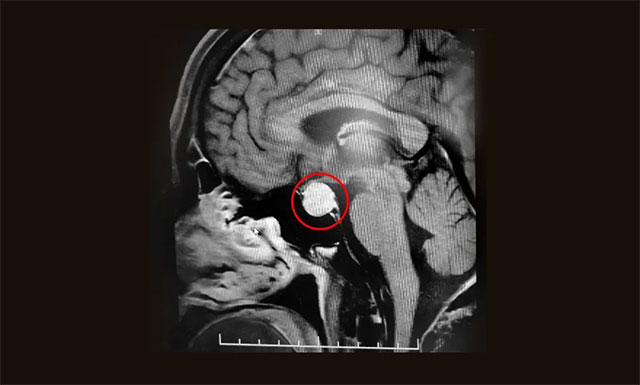

隨后,患者進行了頭部鞍區(qū)MRI平掃+增強,結果顯示:蝶竇顯著擴大,鞍區(qū)見一類圓形腫塊,大小約2.0*1.5*1.3cm。垂體柄縮短、左側偏移;病變向鞍上生長,占據(jù)鞍上池,推移視交叉;向下生長,鞍底受壓變薄;向鞍旁生長、緊貼海綿竇。

▲ 術前MR影像:垂體大腺瘤,超蝶鞍生長

潘仁龍主任指出,垂體腫瘤向鞍上生長,占據(jù)鞍上池,壓迫到視神經(jīng)傳導物,使患者視物出現(xiàn)異常。一般1-3cm的大腺瘤或大于3cm的巨大腺瘤,都會引起不同程度的視力問題。